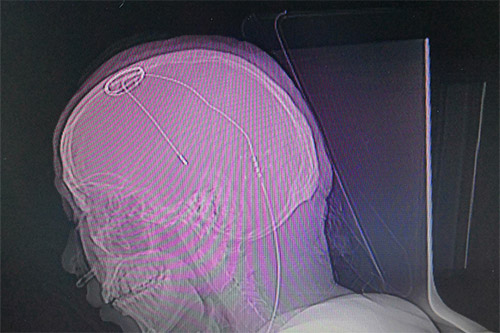

▲患者植入脑起搏器后的影像图

准备就绪后,医生利用磁共振(MR)结合立体定向设备为患者进行影像扫描,再利用手术计划系统进行数据计算,规划手术路径,确定手术的三维立体精准坐标。“电极的直径只有1毫米左右,对手术定位精准度要求非常高,哪怕一点误差都会影响治疗效果。”将手术坐标与患者头部定位支架核对确定后,刘伟钦主任及其团队在患者头部切开了一道切口,并在颅骨打孔,固定好电极基环,最后将电极缓缓植入大脑内丘脑底核处。

电极到达预定位置后,刘伟钦主任对患者进行感觉和运动测试,以直观地评估电极工作情况。患者说话清晰,视力视觉无影响,四肢活动自如,手脚抖动消失,手术效果令人满意,然后对电极位置进行固定。随后对患者进行全身麻醉,将导线经过耳后皮下隧道与置于锁骨下皮下的电池连接固定。术后行CT扫描,将CT扫描数据导入手术计划系统融合、计算,电极与预设手术路径完全吻合,位置准确无误,手术无出血,手术顺利完成。